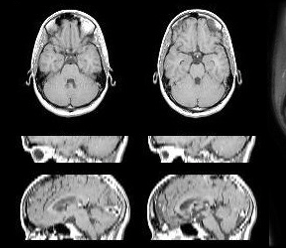

医歯用画像にAIを応用し,診断精度向上と早期疾患予測を実現する手法について研究しています.